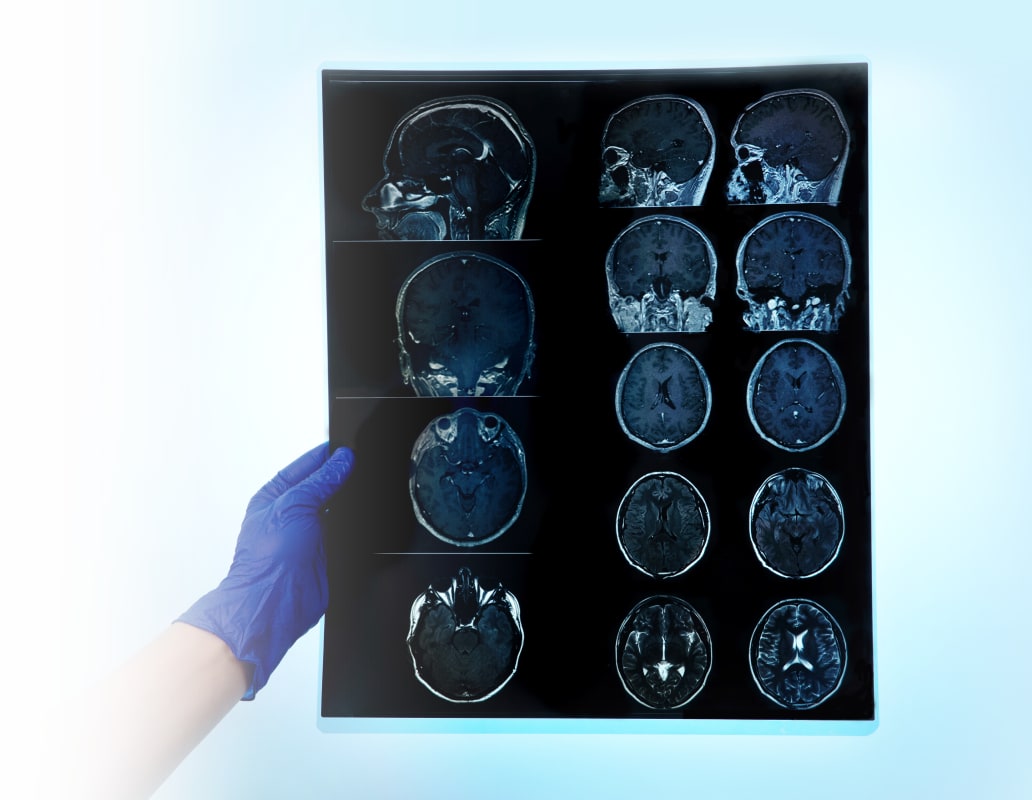

Для постановки диагноза проводится неврологический осмотр. Чтобы выявить изменения глазного дна, характерные для повышенного внутричерепного давления, назначается консультация офтальмолога.

Для визуализации патологии выполняются инструментальные исследования:

- МРТ головного мозга. Для оценки ликворотока может применяться фазоконтрастная ФК-МРТ.

- КТ головного мозга.

Обнаруженная коллоидная киста далеко не всегда требует немедленного лечения. Если образование некрупное и не проявляет себя клинически, врач может выбрать тактику наблюдения. Ежегодное проведение МРТ или КТ позволит оценить динамику процесса, склонность опухоли к росту.

Бессимптомная коллоидная киста может ничем не проявить себя на протяжении всей жизни пациента. Описаны случаи самопроизвольного уменьшения размеров образования. Тем не менее, такие случайные находки требуют регулярного наблюдения. Проходить МРТ или КТ-обследование нужно не реже раза в год. При малейших признаках неблагополучия — головных болях, головокружениях, тошноте, нарушении координации — необходимо немедленно обратиться за медицинской помощью.